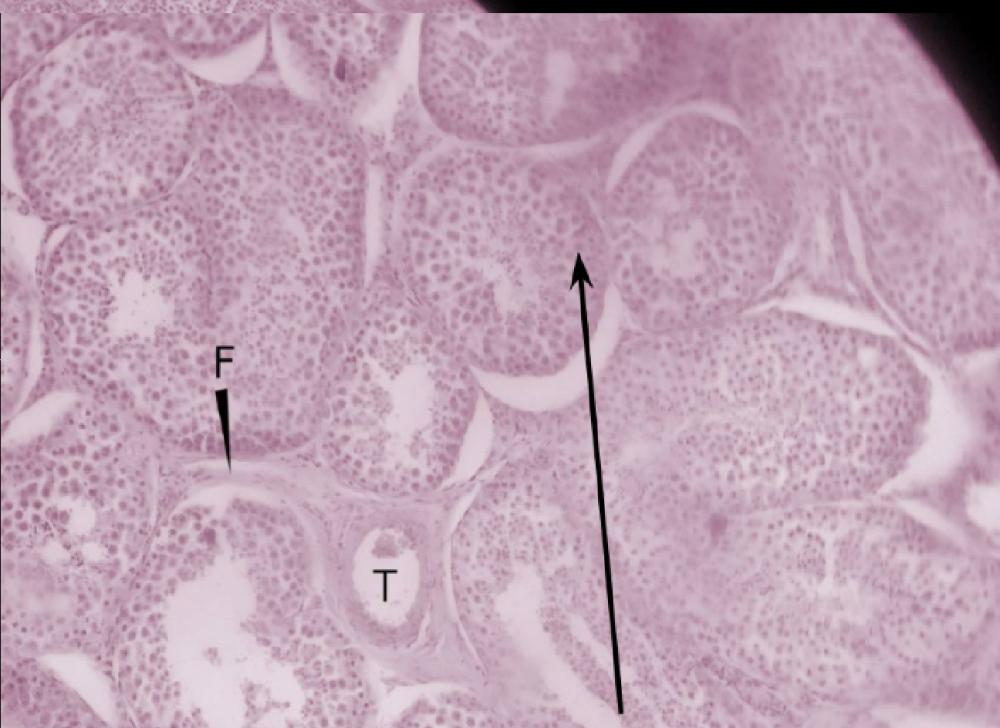

kanalik kręty (jądro)

tkanka łączna zrębu jądra

spermatogonie (jądro)

spermatocyty I rzędu (jądro)

spermatocyty II rzędu/spermatydy (jądro)

plemniki (jądro)

komórki Leydiga (jądro)